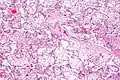

| Micrograph of villous immaturity. H&E stain. | |

Placental villous immaturity is chorionic villous development that is inappropriate for the gestational age.

Immature chorionic villi are larger and have more central blood vessels; thus, the diffusion distance for gas and nutrient exchange is larger and, therefore, placental function is impaired.

High mag.